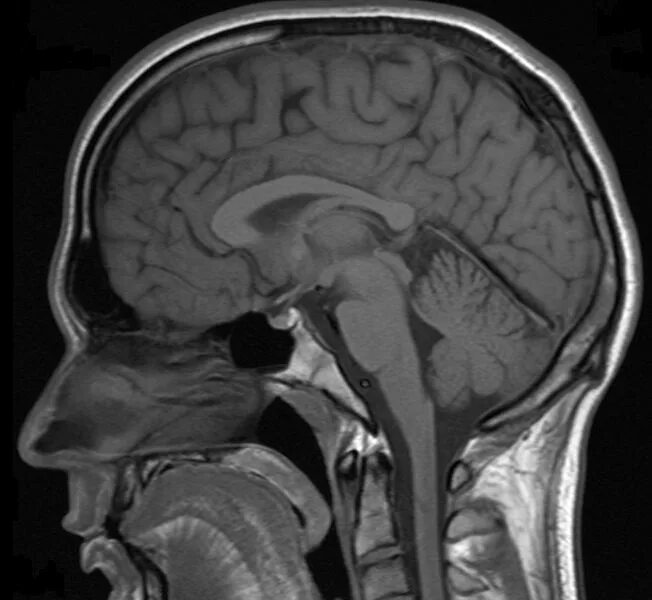

Расширение субарахноидального пространства головного